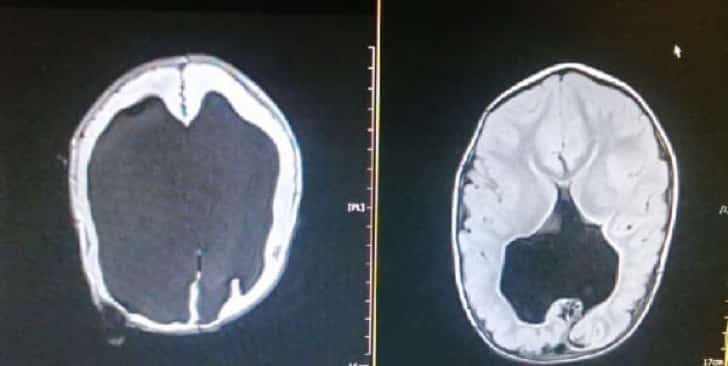

O pequeno tinha hidrocefalia e, como consequência, não somente sua cabeça era muito grande, mastambém quase não possuía cérebro: tinha somente 2%.

Aos quatro anos, os doutores quiseram checar sua condição e o que viram nas radiografias era simplesmente incrível. Noah não era um “milagre” somente por sobreviver… era porque seu cérebro começou a crescer e desenvolver-se.

Noah é um menino realmente feliz. Utiliza uma cadeira de rodas para movimentar-se, canta, fala e nunca deixa de sorrir. Seu cérebro já tem 80% de seu tamanho normal.